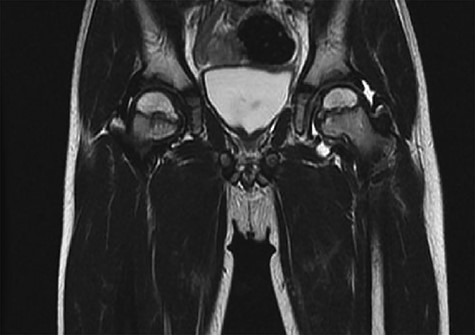

CT hips reported a well-defined lesion seen bilaterally in the neck of femur anterior infero-medial aspect, more prominent on the left side measuring 7 x 3 mm on left side both in coronal (Fig. 3) and axial (Fig. 4) views. On the right side, other lesion measuring 2 x 1 mm (Fig. 5) seen in coronal view. These two lesions are well defined with a sclerotic border with a small cortical defect. The lesion shows fat density. The symmetrical appearance of the lesion combined with the fat density and location suggest the diagnosis of synovial herniation pit. MRI Pelvis revealed minimal left hip joint effusion with loculated fluid seen along the trochanteric bursa with the largest measuring 0.9 x 1.5 cm (Fig. 6, 7).